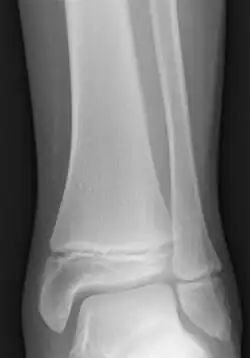

Salter–Harris fractures are fractures involving epiphyseal plates and hence tend to interfere with growth, height or physiologic functions.[12]